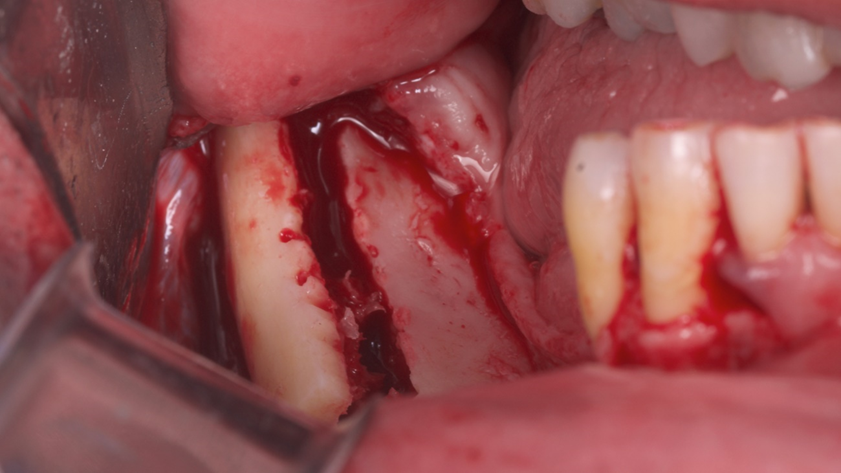

Homem de 60 anos foi encaminhado para reabilitação implantossuportada na região molar inferior direita (Figura 1). O volume ósseo remanescente tridimensional foi acessado por meio de tomografia computadorizada. Revelou uma deficiência vertical de modo que um aumento vertical foi planejado antes da colocação do implante. Seu histórico médico foi verificado e não foram encontradas comorbidades nem condições alérgicas. Não houve achados clínicos intraorais anormais, mas uma deficiência vertical na área molar inferior direita. Nenhum achado anormal foi perceptível no exame extraoral. Um enxerto autógeno em bloco ósseo dividido foi planejado para aumento horizontal e o ramo ipsilateral foi o local doador de escolha. A cirurgia foi realizada sob anestesia local com Articaína 4% e adrenalina 1:100.000. O paciente foi prescrito para enxaguar com Clorexidina 0,12% no pré-operatório, bem como tomar 1mg de Amoxicilina e 8mg de Dexametasona P.O. uma hora antes da cirurgia. Uma incisão mucoperiosteal foi realizada com bisturi número 15C desde o ramo mandibular até a borda mesiovestibular do primeiro pré-molar juntamente com uma incisão perpendicular obliquamente no vestíbulo mandibular. Após o descolamento da mucosa vestibular e liberação do nervo mentoniano, a mucosa lingual também foi descolada (Figura 2). Duas osteotomias verticais e uma horizontal foram realizadas no ramo mandibular com broca 701 para retirada do bloco ósseo necessário à reconstrução horizontal (Figura 3). Após a retirada do enxerto com auxílio de um elevador radicular, o bloco foi cortado longitudinalmente em dois pedaços finos com brocas discais e o osso esponjoso foi raspado para que pudesse ser utilizado como osso lascado (Figuras 4 a 8). Os blocos foram fixados na área edêntula. Um bloco foi fixado na face vestibular e o outro na face lingual. Cada um deles foi fixado com dois parafusos de osteossíntese de 1,5 mm e o osso lascado foi inserido no espaço entre eles (Figuras 9 e 10). A ferida foi fechada com fio de polipropileno 5-0, que foi retirado após 15 dias (Figura 11). A cirurgia cicatrizou sem intercorrências e o paciente recebeu prescrição de amoxicilina 500 mg P.O. a cada oito horas durante sete dias e ibuprofeno 600 mg a cada seis horas durante cinco dias.